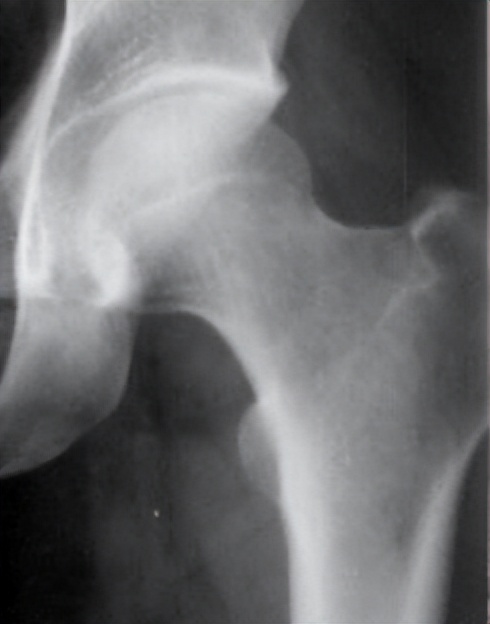

2.ARCO Ⅱ期~ⅢA期:

本期特点:坏死偏于负重区,可见软骨下骨折或坏死区骨折,范围>1/3,塌陷<2mm。

手术方法2:微创*压打**植骨、异体腓骨支撑内固定术

技术特色:在钻孔减压清除死骨的同时,通过骨隧道用松质骨*压打**植骨充实,纠正及预防塌陷,再用异体腓骨植入,螺钉挤压固定腓骨。手术把死骨清除与恢复骨量、重建稳定、纠正塌陷、提供力学支撑融为一体。该术式较切开关节手术具有创伤小、对关节的干扰及局部血运破坏少、功能康复快等优点。